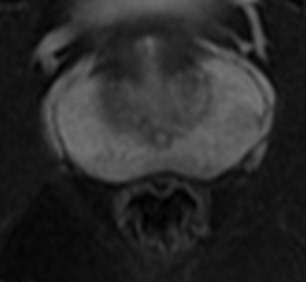

前列腺-fs T2